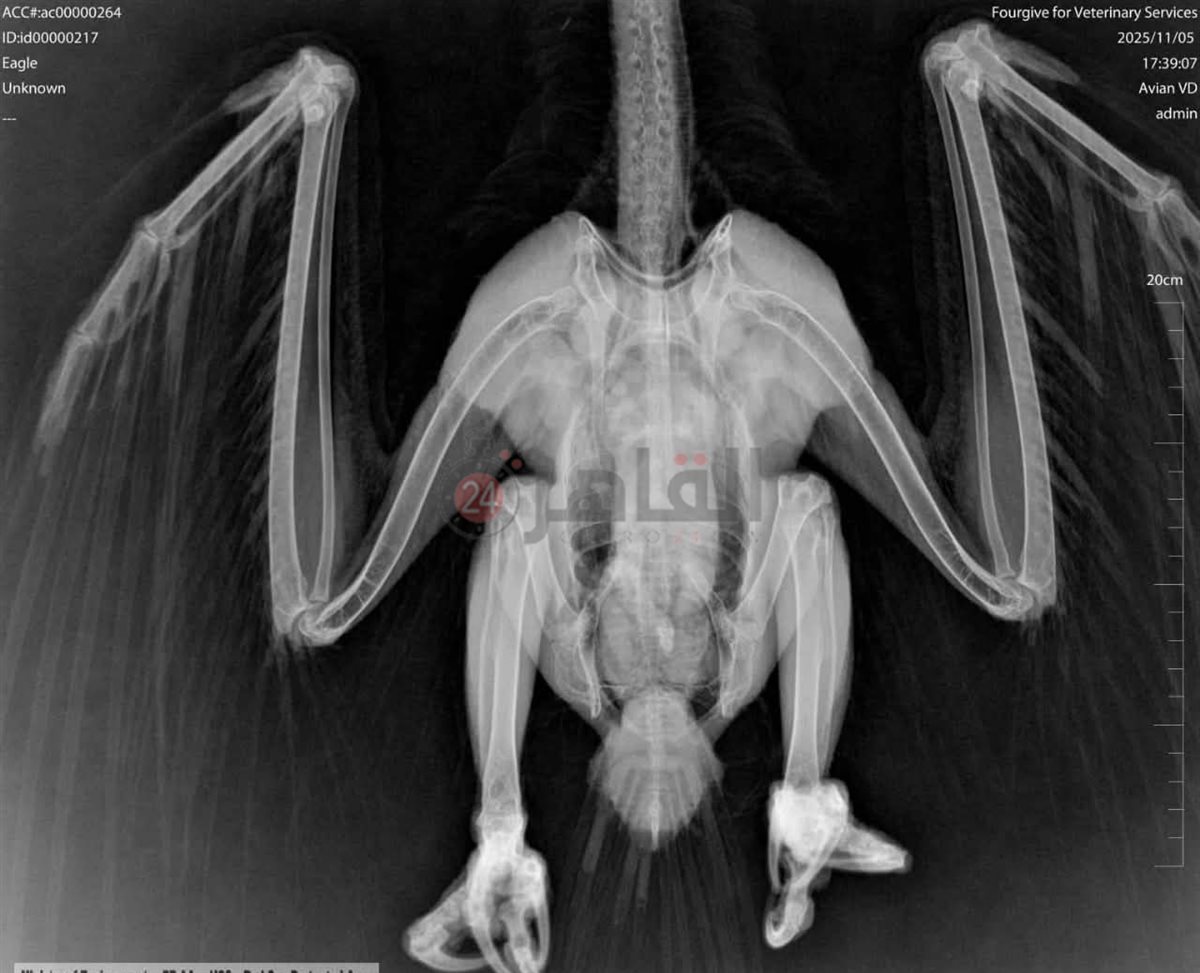

على الفور تم تشكيل لجنة متخصصة لعلاج الطائر، بالتعاون مع احدي العيادات الطبية حيث تم إجراء فحوصات سريرية وعمل أشعة X-Ray.

وأظهرت الفحوصات عدم وجود كسور، بينما تبيّن إصابة الطائر بـطفيليات جلدية استدعت تلقي علاجًا متخصصًا، وخلال فترة المتابعة داخل العيادة، شهدت حالة الطائر تحسنًا ملحوظًا.